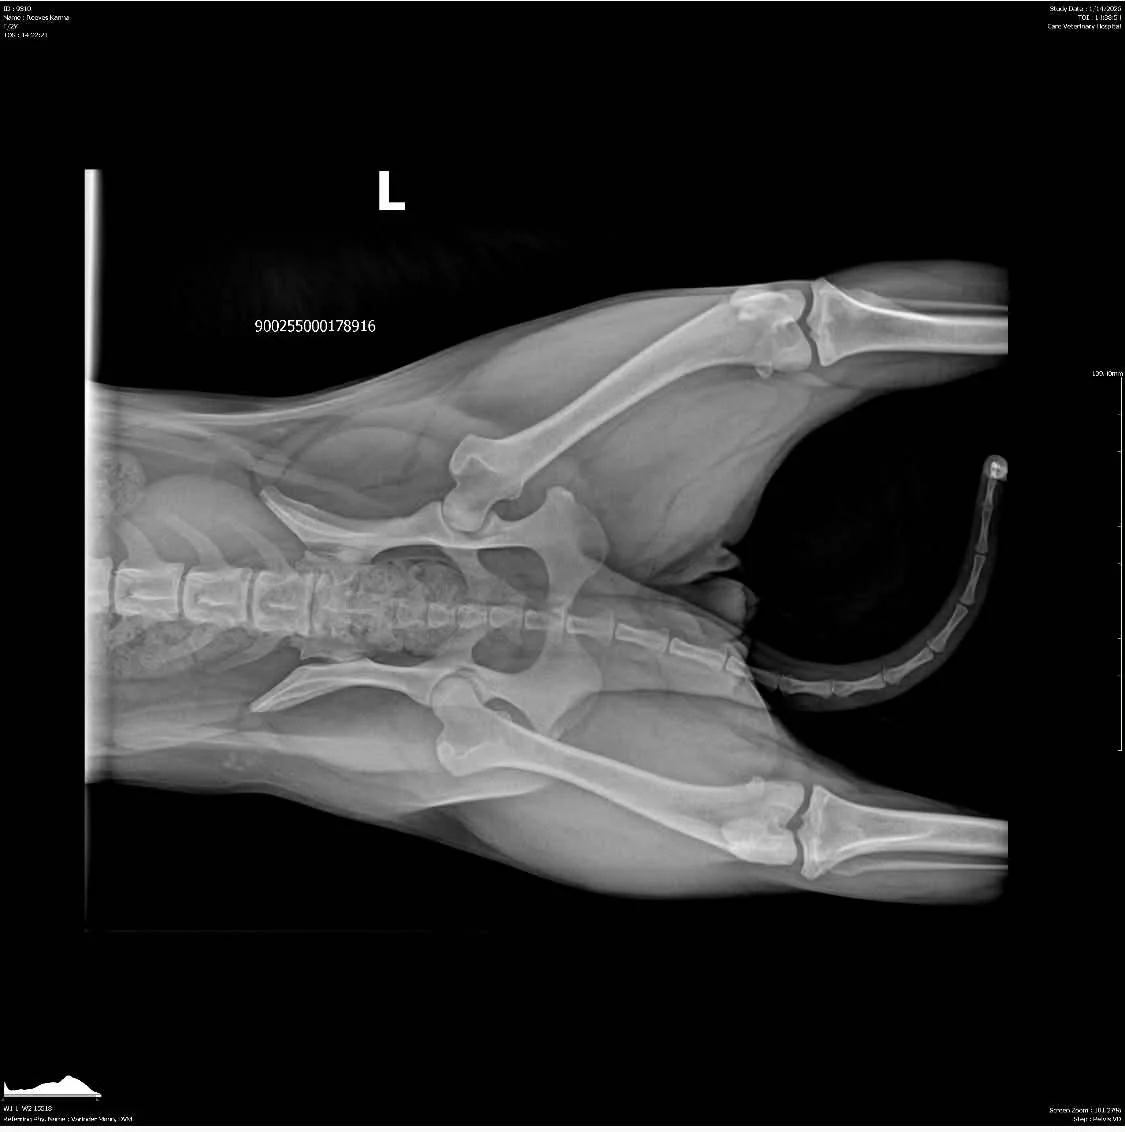

OFA Hips: Clear by parentage, scheduled for fall 2025

OFA Elbows: Clear by parentage, scheduled for fall 2025